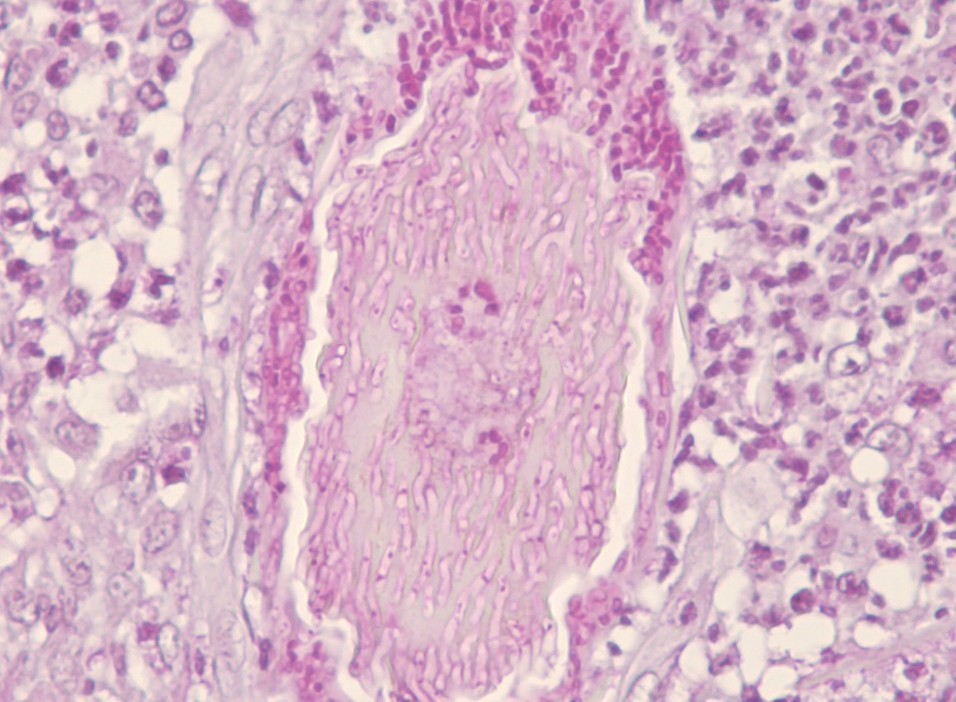

La biopsia del punch è stata prelevata dalla pelle nell’area periauricolare. L’esame istologico ha rivelato un’infiammazione grave, nodulare, piogranulomatosa e perifollicolare con foruncolosi multifocale. Elementi fungini (spore e ife) sono stati identificati nella sezione colorata di routine con ematossilina ed eosina (H&E). La loro presenza è stata confermata dalla colorazione Periodic acid-Schiff (PAS). I risultati istologici erano compatibili con un’infezione fungina superficiale della pelle – dermatofitosi (fig. 4A e B).

- Figura 4A: Dermatofitosi su cute con pelo di un cane: spore fungine e ife intorno ai fusti piliferi nei follicoli piliferi e foruncolosi; 20x, colorazione ematossilina e eosina (H&E) (A); 40x, colorazione Periodic acid–Schiff (PAS) (B)

- Figura 4B